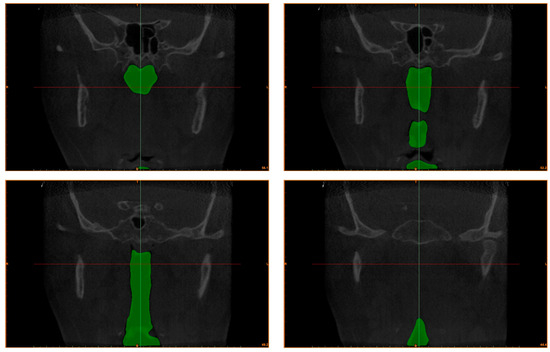

3.1. Cross-Sectional Area

| Responder 1 | Responder 2 | Diff (%) | ||

| Cross-sectional area | 7.68 mm2 | 5.42 mm2 | 29.47% | |